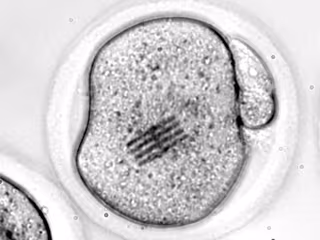

El dispositivo en el interior de un óvulo.

El dispositivo en el interior de un óvulo. - CSIC

En su trabajo, publicado en la revista 'Nature Materials', los científicos han inyectado el chip en el interior de un óvulo de ratón junto con un espermatozoide para estudiar las etapas iniciales de la fertilización. El dispositivo, que funciona como sensor mecánico, mide apenas 22 por 10,5 micrómetros, tiene un grosor de 25 nanómetros (tres veces menor que el de un virus como el SARS-CoV-2) y una longitud 3 veces más pequeña que el diámetro de un cabello humano.

"Nosotros vemos a través de microscopia óptica cómo el chip se dobla en el interior de la célula". "Dado que conocemos perfectamente qué fuerza hay que aplicar para que se doble el dispositivo de una determinada manera, y lo hemos modelizado, visualizar la curvatura nos permite inferir qué fuerzas mecánicas se están dando en el interior de la célula", añade Plaza.